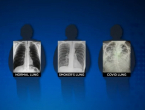

Liječnica uporedila pluća poslije koronavirusa i pluća pušača

15.01.2021 17:05 Promjene na plućima